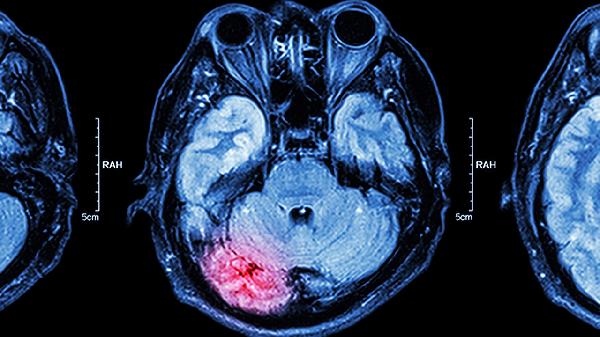

新生儿颅内感染的危险期通常发生在出生后的数小时至数天内。这一时期因个体差异而异,主要受感染源类型和感染程度的影响。由于新生儿的免疫系统尚未完全发育,他们对感染的抵抗力较弱,容易受到细菌、病毒或其他病原体的侵袭,导致脑膜或脑实质发生炎症。

3、临床表现的监测:家长和医护人员需要密切监测新生儿的临床表现。常见的症状包括频繁的惊厥、呕吐和嗜睡等。这些症状可能是颅内感染的早期信号,及时识别和处理可以有效减少并发症的发生。